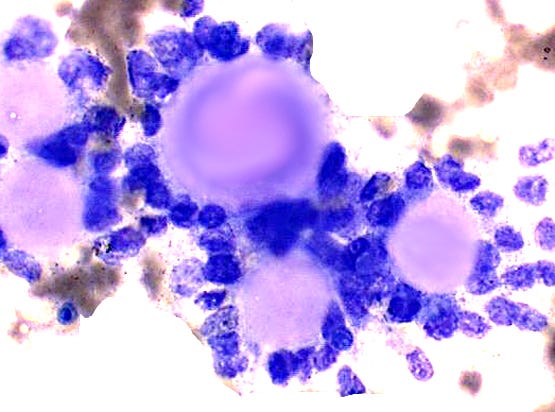

Fine needle aspiration cytology shows clusters of epithelial cells oriented around solid spheres of basement membrane material.

Adenoid cystic carcinoma of the breast - microscopic and cytologic images